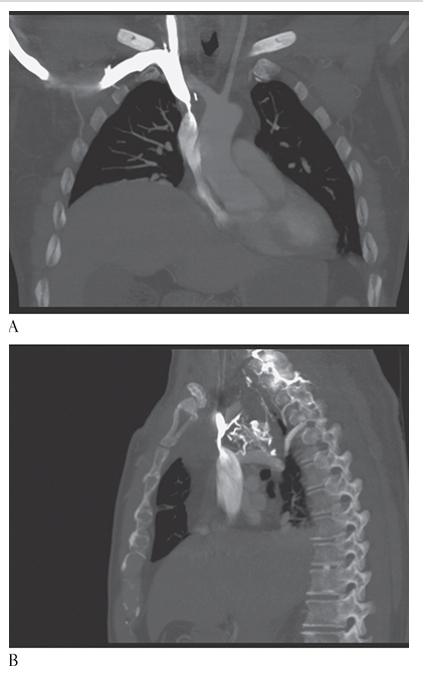

What is A

Lung Contusion. CECT axial coronal MPR

What is B

Lung Contusion. CECT axial and sagittal MPR

What is C

Lung Contusion. CECT axial images of a trauma patient showing the extensive pulmonary contusion of the right upper and lower lobes. There is confluent lung opacification with multiple small posttraumatic pneumatoceles.